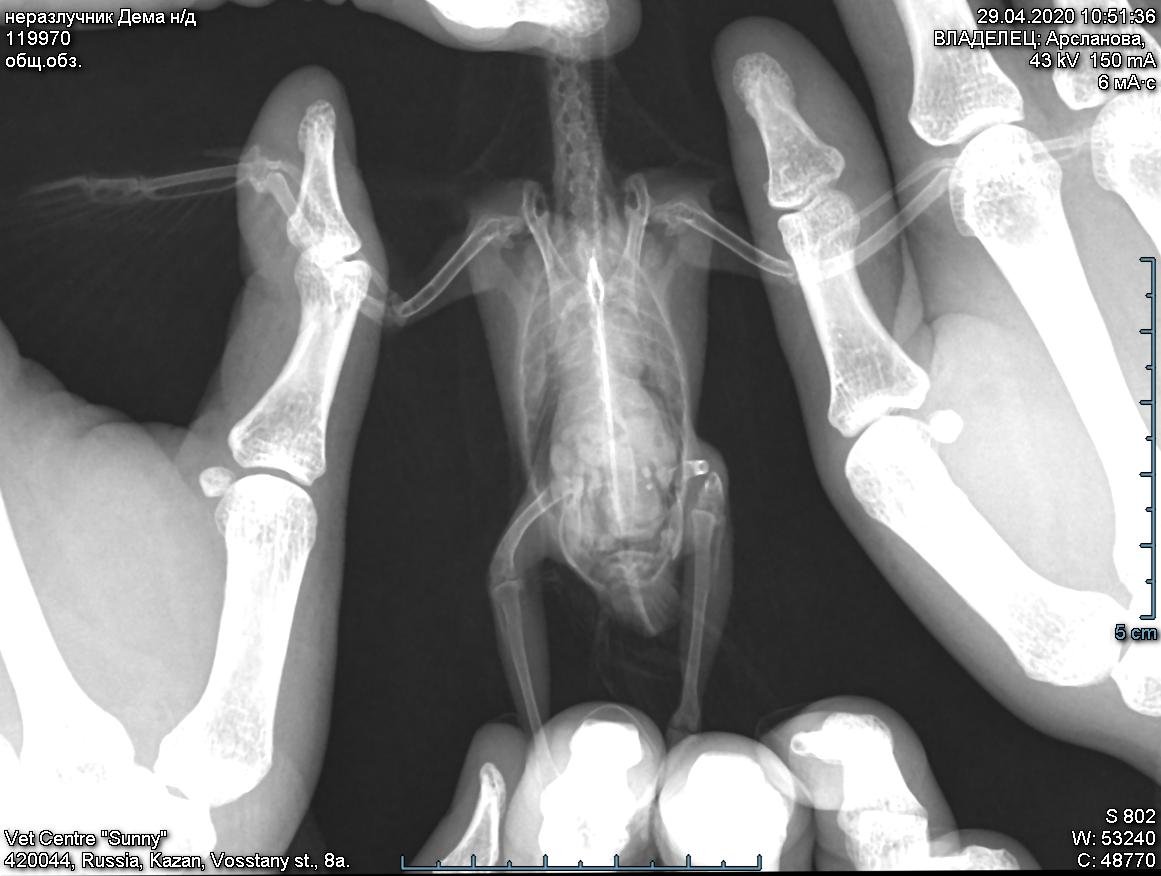

прилагаю заключения и рентген.

Уважаемая @Zosia , прошу посмотреть.

левая лапа отказавшая так и остается  слабой, а правая, которая сохраняет хватательный эффект, на рентгене показала перелом (?)

неразлучни_нд_2020-04-29_10-51-36_общ_обз_.jpg

Да,левое бедро...

И вообще странные косточки лап(пальцев)- зоны воспалений точечные,неравномерной плотности (не получается увеличить,на пиксели все распадается).

@Zosia на очном осмотре специалист говорила, что перелом может быть давним. перелом левого бедра не прощупывается. левой лапой работает сейчас, все пальцы функционируют.